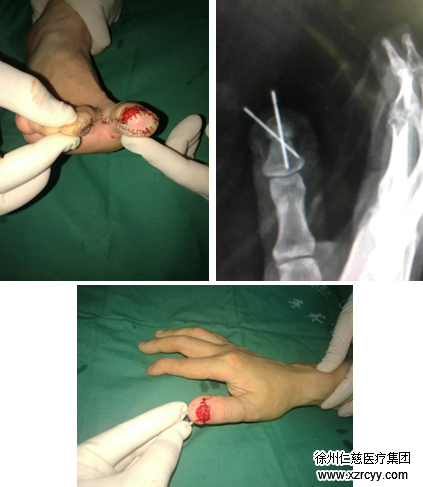

手术过程中,医生为患者清除伤指创缘挫伤、污染失活组织,术后予抗感染、换药对症治疗。一周后,王师傅的伤手具备了再造手术指征,手术团队运用成熟的显微外科技术、整形外科技术为其进行了“右拇指清创再造术”。

手术小组先根据伤指缺损情况设计好游离皮瓣的大小和形状,然后从患者右脚大脚趾位置小心地对应标明拇指缺损的大小,之后将脚趾相关部分切下,并将脚趾血管、神经毫无损伤地游离取下,再与拇指的血管、神经对应接好,使二者相互吻合。此外,对于右足第一趾残缺的部分,手术小组又小心选取右足第二趾岛状皮瓣,覆盖于第一趾创面,将第二趾创面直接缝合。

手术漂亮地完成了,王师傅右手拇指外观和原来类似,存活良好,恢复到原先的能力。至于神经感觉的恢复,一般需要在术后3个月后逐渐恢复起来。